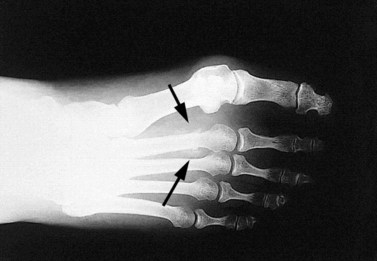

Pain may be produced over the superficial fracture site by vibration. This may be produced from a tuning fork or ultrasound unit (Lowden, 1986), and is generally of more use in low risk areas, such as the foot and shin. Where there is a risk of complication through displacement (such as in the neck of the femur) bone scan with possible surgical intervention may be more appropriate (Fig. 10.14).

image

Figure 10.14 X-ray of stress fracture.

From Read (2000) with permission.